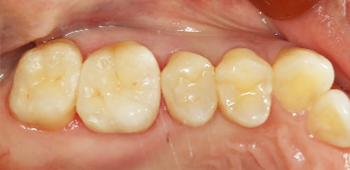

虫歯の治療も現在はセラミックの治療が最も良いとされています。

銀の詰め物と比較して『精度』が良く、再度虫歯になるリスクが低いです。

当院のセラミック治療は適合も良く、セメントも歯と化学的に接着するものなので細菌の侵入を防ぐことが出来、さらに審美的です。

| 治療期間 | 2週間 |

|---|---|

| 費用 | セラミックインレー 6万6千円(顕微鏡治療の場合10万円) |